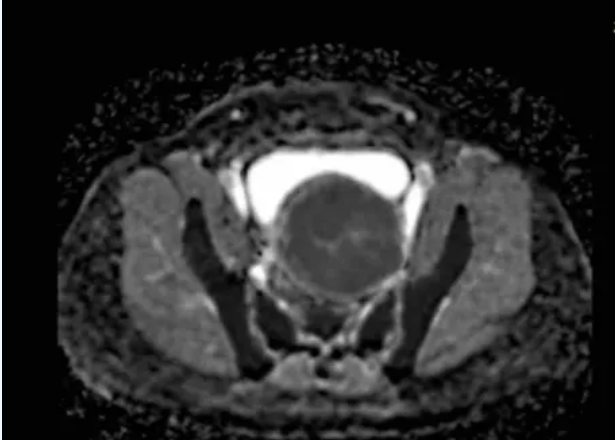

术前MRI平扫及增强扫描可鉴别子宫肌瘤与隐匿性子宫平滑肌肉瘤。弥散加权成像(DWI)高信号、表观弥散系数(ADC)低信号及强化不均是子宫肉瘤的典型影像学表现;MRI的T2加权成像(T2WI)信号可评估消融难度,若T2WI高信号则提示肌瘤含水量高,消融难度通常大于T2WI低信号的病灶。

图:MRI显示肿瘤的ADC值较低